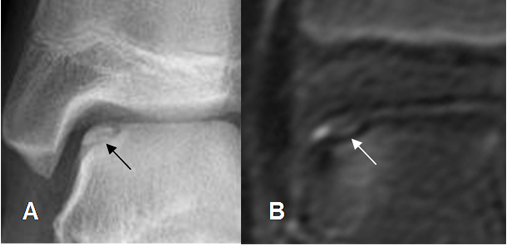

Fig 39. Lesión osteocondral estado I.

A: Rx AP y B: RM axial en T1. Lesión por compresión de la parte

superointerna del talo.